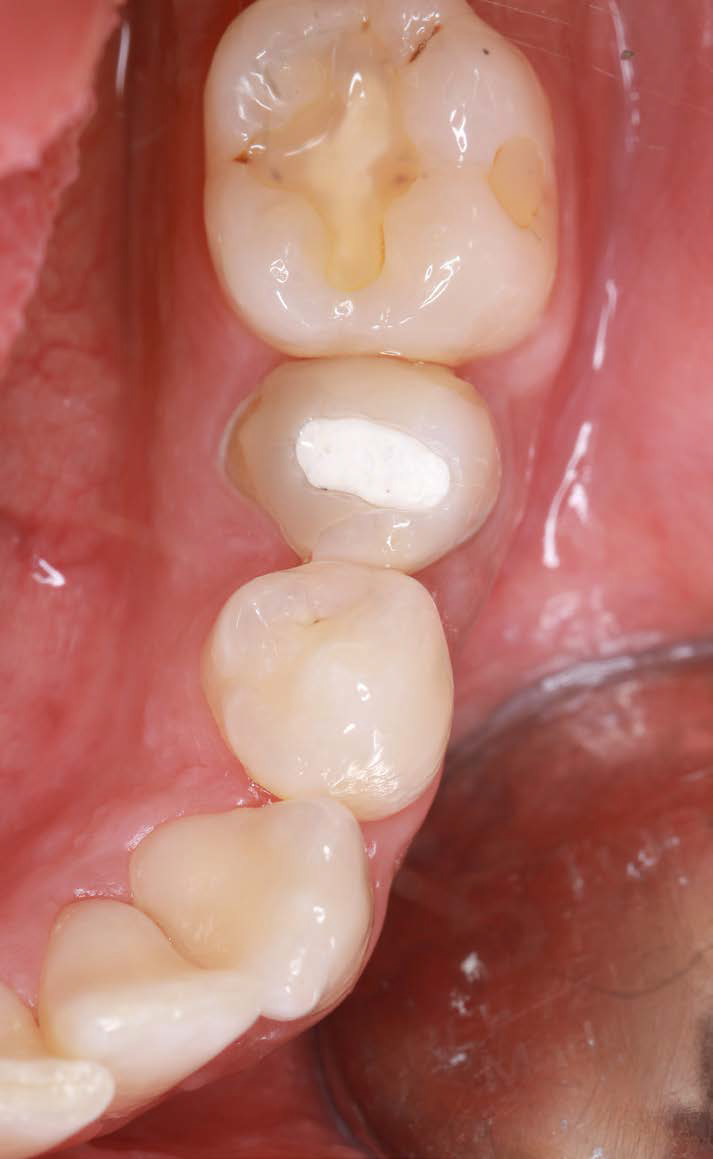

After osteotomy, I placed a 3.75 mm diameter implant, filled the gap between implant and root surface with allogenic bone substitute, inserted a provisional, and later restored with an aesthetic ceramic crown.

Figure 9: Clinical image after prosthetic restoration |

After six months, the soft tissue remained stable, and the papillae were well-formed. The case met all expectations for “pink-white aesthetics.” I was very satisfied with both the surgical and prosthetic results.